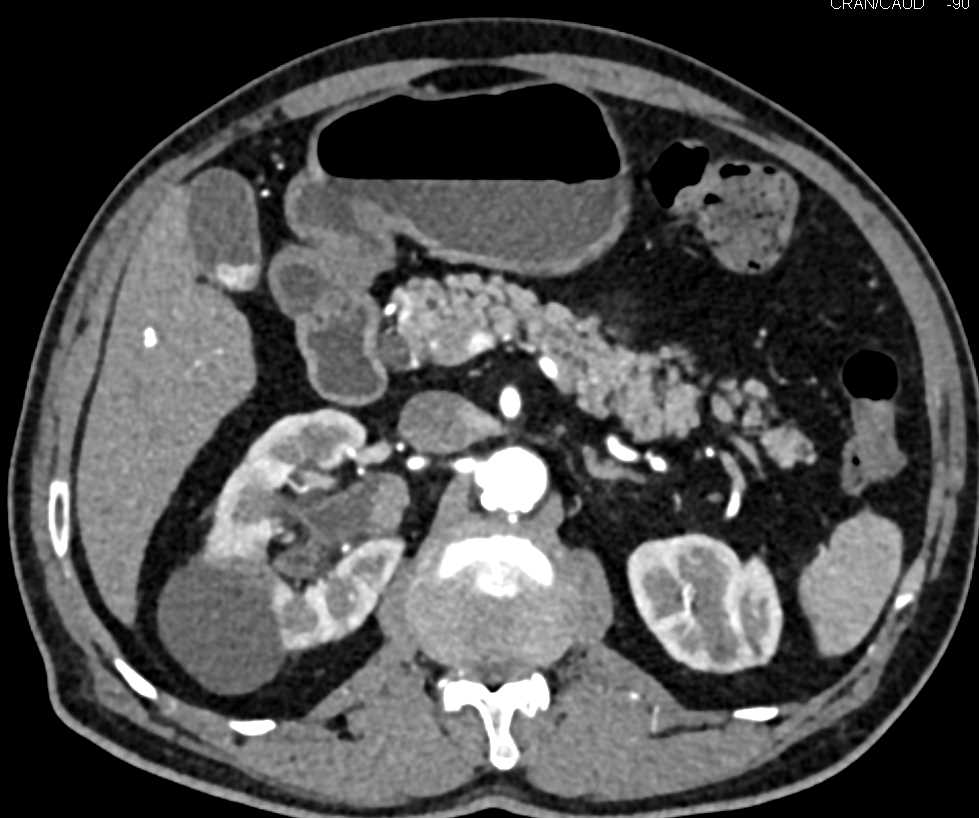

Transitional Cell Carcinoma Right Kidney and Bladder